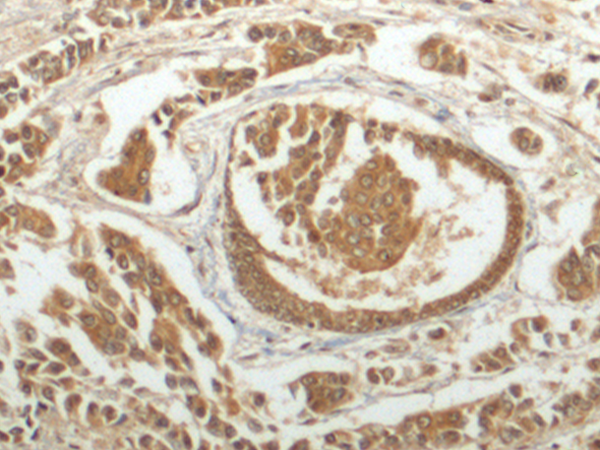

ELISA, IHC |

IHC positive control: |

Human breast cancer and Human tonsil |

IHC Recommend dilution: |

150-300 |